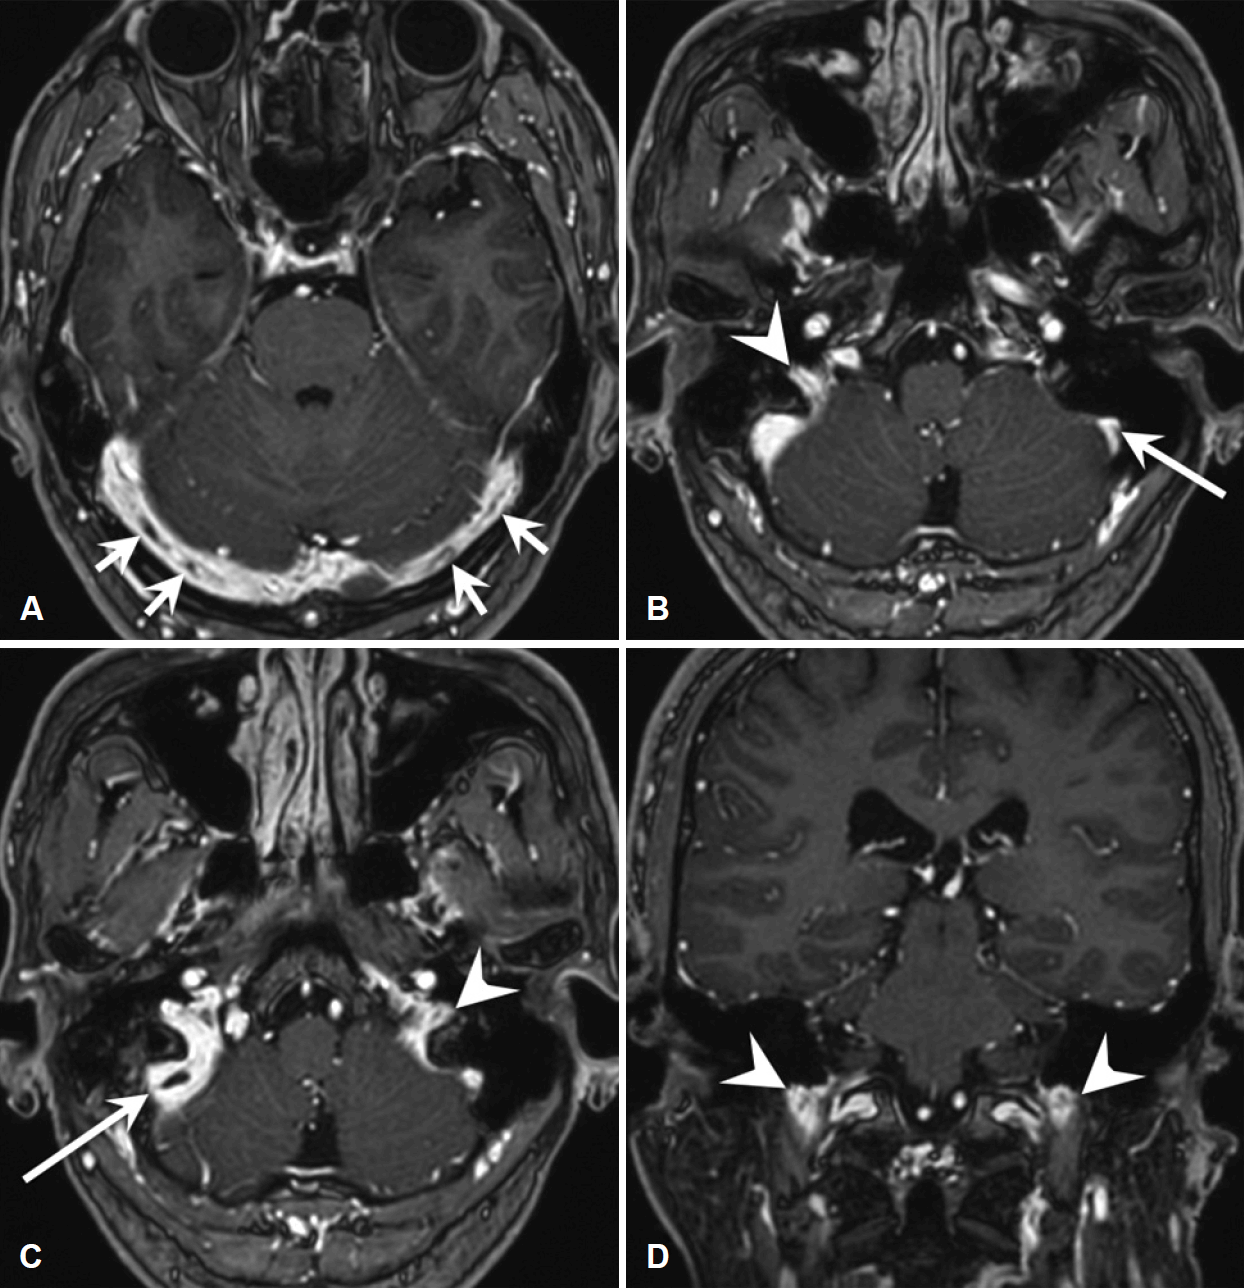

Gadolinium-enhanced T1-weighted MRI of the brain. The axial (A–C) and coronal (D) images show multiple partial filling defects suggesting dural venous sinus thrombosis in both transverse sinuses (short arrows), sigmoid sinuses (long arrows), and internal jugular veins (arrowheads). The right dural venous sinuses are the dominant venous drainage in this patient.

A 46-year-old male presented to our outpatient clinic with dizziness that had started 3 weeks earlier. His medical, surgical, and family histories were unremarkable. The dizziness was characterized as a whirling sensation that lasted for several hours regardless of posture, and lightheadedness that continued even after the acute symptoms had resolved. He had experienced four episodes of vertigo during the 3 weeks since onset, none of which had lasted for more than 12 hours. The dizziness was accompanied by aural fullness and tinnitus of the right ear, followed by nausea and vomiting. At the time of the visit, his aural fullness had partially improved, and the results of pure-tone audiometry at low frequencies were normal. Vestibular assessment by videonystagmography revealed spontaneous nystagmus on the right side in all positions, but the bithermal caloric test showed normal caloric responses. Downbeat nystagmus was evident in the spontaneous nystagmus test and right-sided Dix-Hallpike test, but not in the roll test or left-sided Dix-Hallpike test. The vestibular evoked myogenic potential was normal, and there was no catch-up saccade in the video head impulse test (vHIT). The ratio of the summating potential (SP) to action potential (AP) measured by electrocochleography (ECoG) was abnormal on the right (0.375) and normal on the left (0.212) (Fig. 1). Based on these findings, we diagnosed the patient with probable acute-stage Ménière’s disease associated with irritative nystagmus. He was hospitalized for medical management of his symptoms, and initially treated with thiazide diuretics, betahistine, and a vestibular suppressant. On the third hospital day, he complained of blurred vision and a feeling of increased intraocular pressure. After additional detailed history-taking, we found that his visual symptoms accompanied the onset of dizziness and had worsened after hospitalization. The remainder of the neurological examination was normal. An ophthalmic consultation detected bilateral optic disc edema, confirming the papilledema with suspected IICP. Contrast-enhanced MRI of the brain was performed to exclude central lesions and showed multiple tubular and linear filling defects in the distal superior sagittal sinus, both transverse sinuses, sigmoid sinuses, and internal jugular veins (Fig. 2). Additional serological and routine blood markers were normal, including the peripheral white blood cell (WBC) count, the erythrocyte sedimentation rate (ESR), the levels of C-reactive protein (CRP), anti-phospholipid and anti-cardiolipin antibodies, and proteins C and S, the Leiden factor V mutation and a prothrombin mutation, and the levels of antithrombin III, factor VIII, and D-dimer. After neurological consultation, anticoagulation therapy was considered because CVST was thought to be the cause of the IICP. As there were no parenchymal lesions or other symptoms, the novel oral anticoagulant rivaroxaban (20 mg once daily) was started. Antibiotics were not prescribed because there was no evidence of acute infection. After treatment, the nystagmus improved within a few days, as did the dizziness and aural fullness. Initial medications were stopped early after confirming that symptoms had resolved, and anticoagulant treatment was continued. An ophthalmic examination performed after 3 weeks of treatment showed improvement of the papilledema. Currently, anticoagulation therapy has been maintained for more than 3 months, and there has been no symptom recurrence on follow-up.

Our patient lacked the headache and fever that are typical symptoms of CVST. On MRI, the thrombosis exhibited partial filling defects without venous infarcts. In addition, the onset of ophthalmic symptoms was delayed until several days after the onset of vertigo. Thus, we suggest that there were no related symptoms typical of CVST because it did not completely block venous flow. Aural fullness and tinnitus were evident only in the right ear, and the SP/AP ratio of the right ear was increased to 0.375, whereas that of the left ear was normal. On MRI, the transverse sinus, sigmoid sinus, and internal jugular vein showed similar degrees of thrombus on both sides, so it would be difficult to explain the difference between the two sides based on the extent of the thrombus. However, as the right venous drainage system was dominant in this patient, the possibility of more severe right-sided venous congestion despite a similar degree of thrombus might have resulted in the right-sided symptoms.